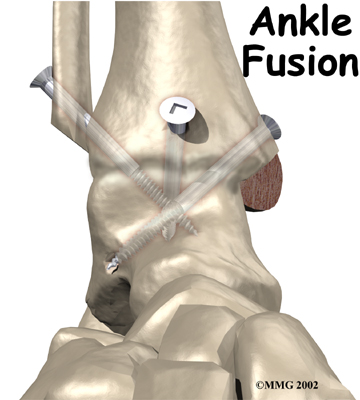

It is important when the surfaces are removed that the angles of the cut surfaces are correct. When the tibia is brought against the talus, the foot should be at a right angle to the lower leg. Once the cuts are made the bones must be held in place while they fuse. This can be done using large metal screws and metal plates if necessary. The screws are usually under the skin and are not removed unless they begin to rub and cause pain.

Inserting the screws